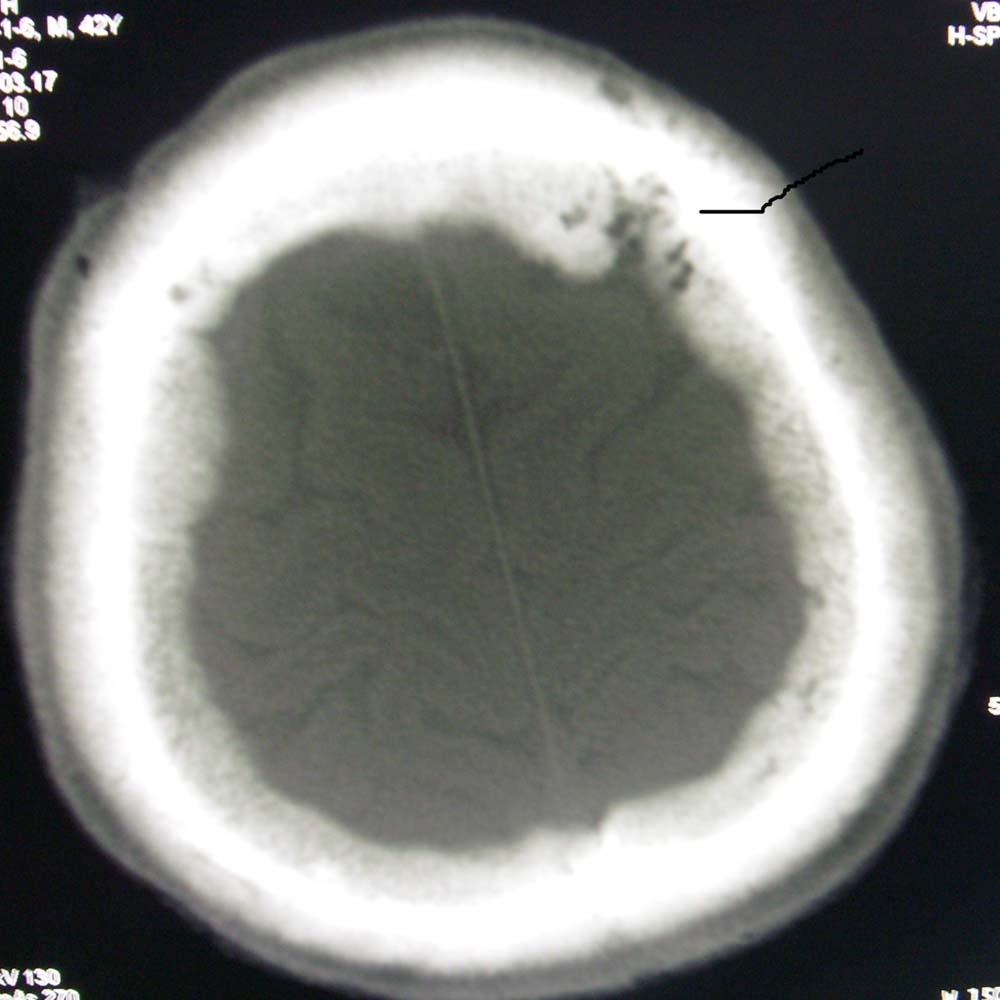

男,45,外伤体检,请问骨窗最后一层板障内低密度影是正常吗

蛛网膜颗粒压迹.

蛛网膜颗粒压迹。

蛛网膜颗粒压迹,为正常表现。